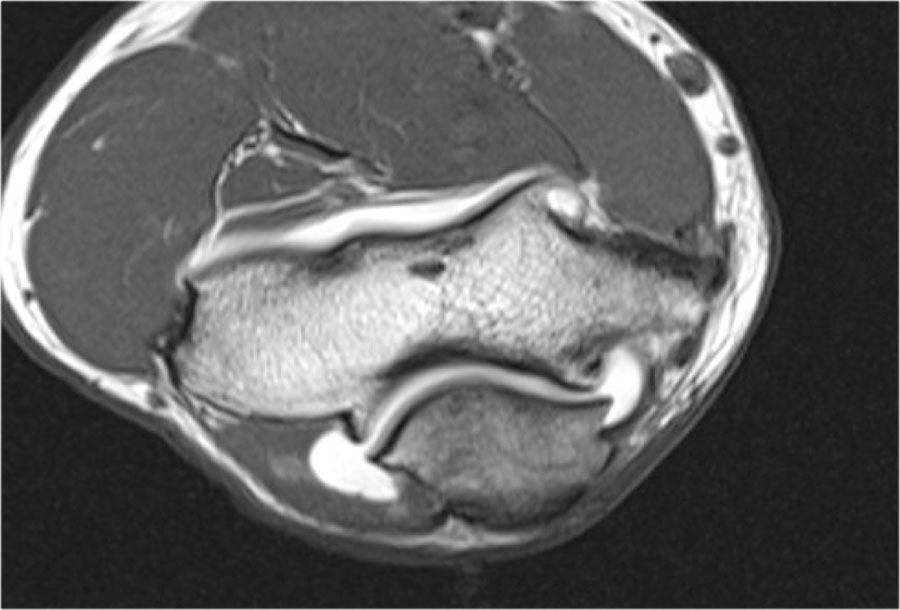

Hình chụp X-quang của một vận động viên bóng chày 15 tuổi với tiền sử đau khuỷu tay 4 năm và gần đây có triệu chứng kẹt khớp.

Có một vùng thấu quang khu trú ở chỏm con và một số mảnh vỡ.

Đây là hình ảnh điển hình của tổn thương sụn xương chỏm con và hiện tượng kẹt khớp có thể là kết quả của các dị vật trong khớp.

Continue with the MR…

MR-arthrogram xác nhận tổn thương sụn xương.

Có gadolinium nằm giữa xương cánh tay và tổn thương sụn xương, cho thấy tổn thương này không ổn định.

Nếu không có gadolinium, hãy tìm dịch khớp chui xuống dưới mảnh sụn xương.

Có một mảnh thể tự do trong ngách sau của khớp quay-cánh tay.

Notice also the fragmentation as seen on the axial image.